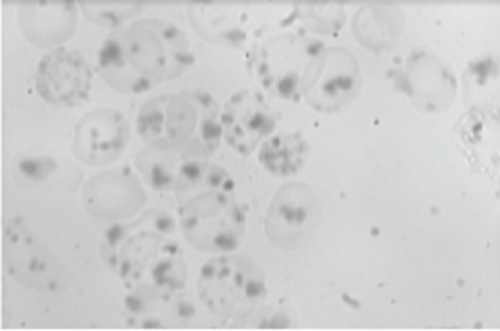

Pemeriksaan apus darah tepi dapat memberi gambaran penyebab anemia. Pada anemia hemolitik, sediaan apus darah tepi dengan pewarnaan rutin dapat menunjukkan polikromasia, pertanda peningkatan produksi sel darah merah.[2,4]

Dengan pewarnaan supravital (Heinz body prep), dapat ditemukan badan Heinz pada kasus anemia hemolitik akibat defisiensi G6PD. Namun, badan Heinz juga dapat ditemukan pada kondisi hemoglobin tidak stabil, seperti hemoglobin Köln. Untuk membedakannya, dapat dilakukan prosedur denaturasi panas.[2,4]

Gambar 1. Badan Heinz dalam eritrosit pada pemeriksaan apus darah tepi. Sumber: Anonim, Openi, 2015.